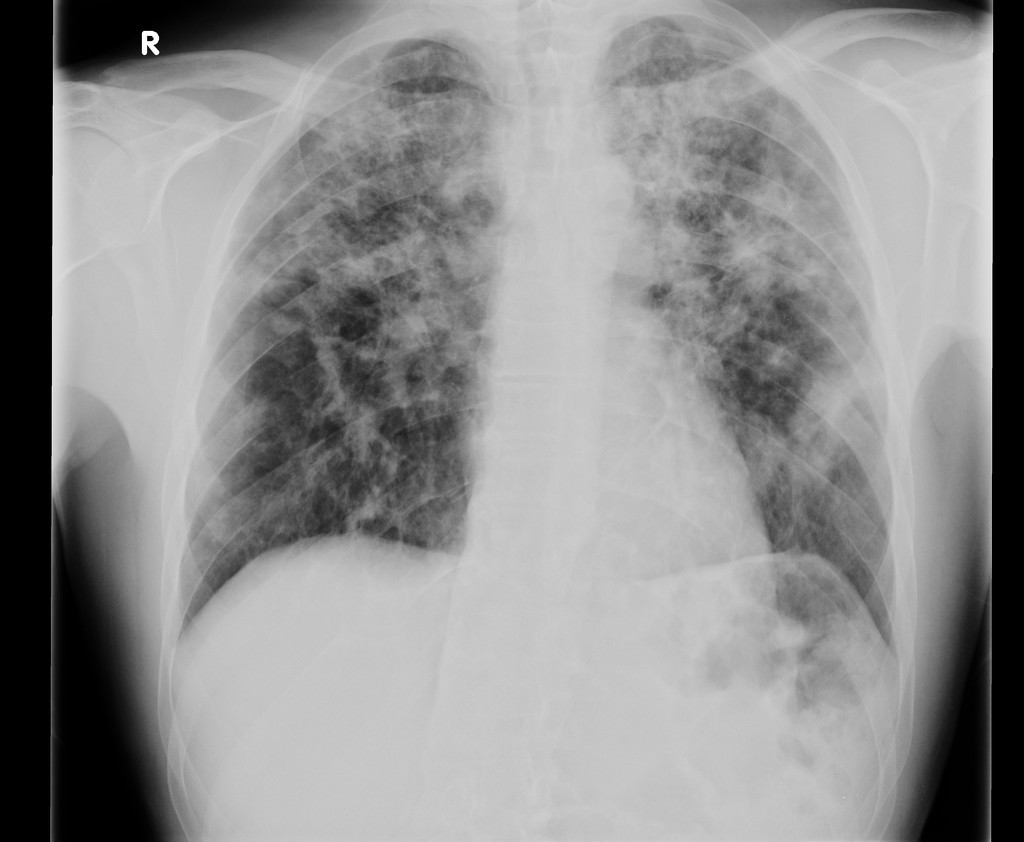

HOMEM DE 20 ANOS COM QUADRO DE INSUFICIENCIA RESPIRATÓRIA E HEMOPTISE. NEGA FEBRE

OPACIDADES DIFUSAMENTE DISTRIBUÍDAS, COM PADRÃO SUGESTIVO DE PREENCHIMENTO ALVEOLAR, PREDOMINANTE EM LOBO INFERIOR DIREITO

HEMORRAGIA ALVEOLAR